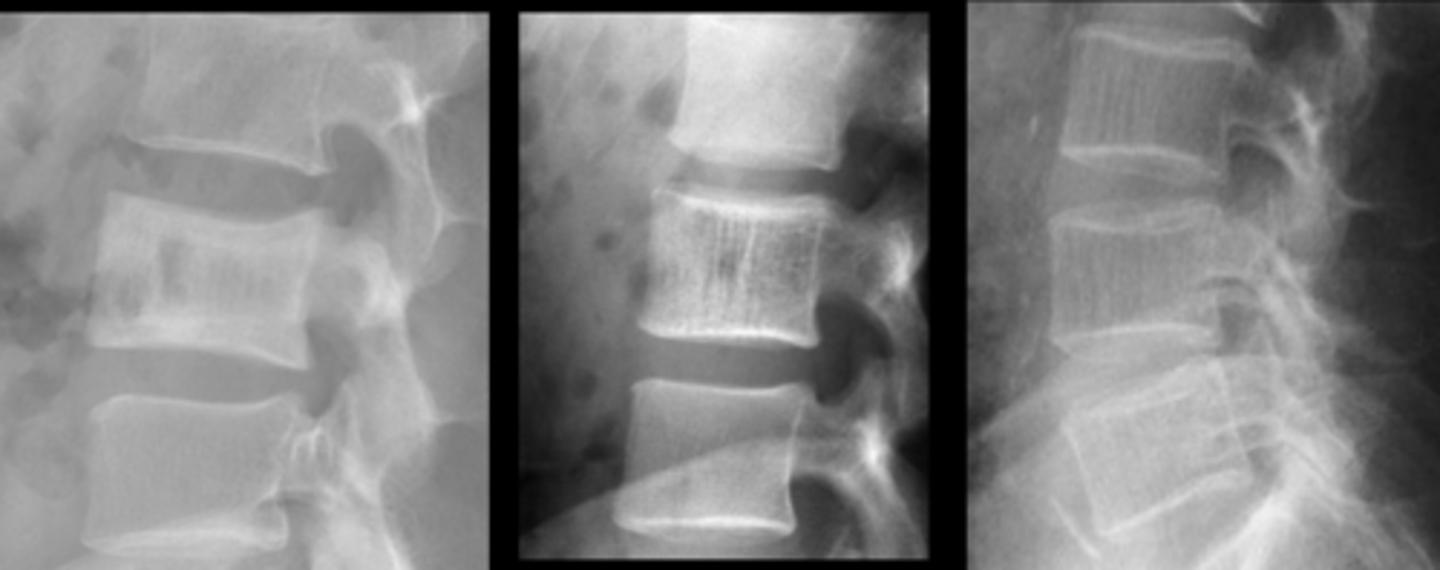

- Left: Paget Disease

- Middle: Vertebral hemangioma

- Right: Osteoporosis

Complete the DDx for vertebral hemangioma

<p>Complete the DDx for vertebral hemangioma</p>

- Vertical striations (corduroy cloth)

- Expansion (rare) may result in neurologic findings

- Skull ("sand dollar")

- Paravertebral swelling

State the radiographic features of vertebral hemangioma

<p>State the radiographic features of vertebral hemangioma</p>